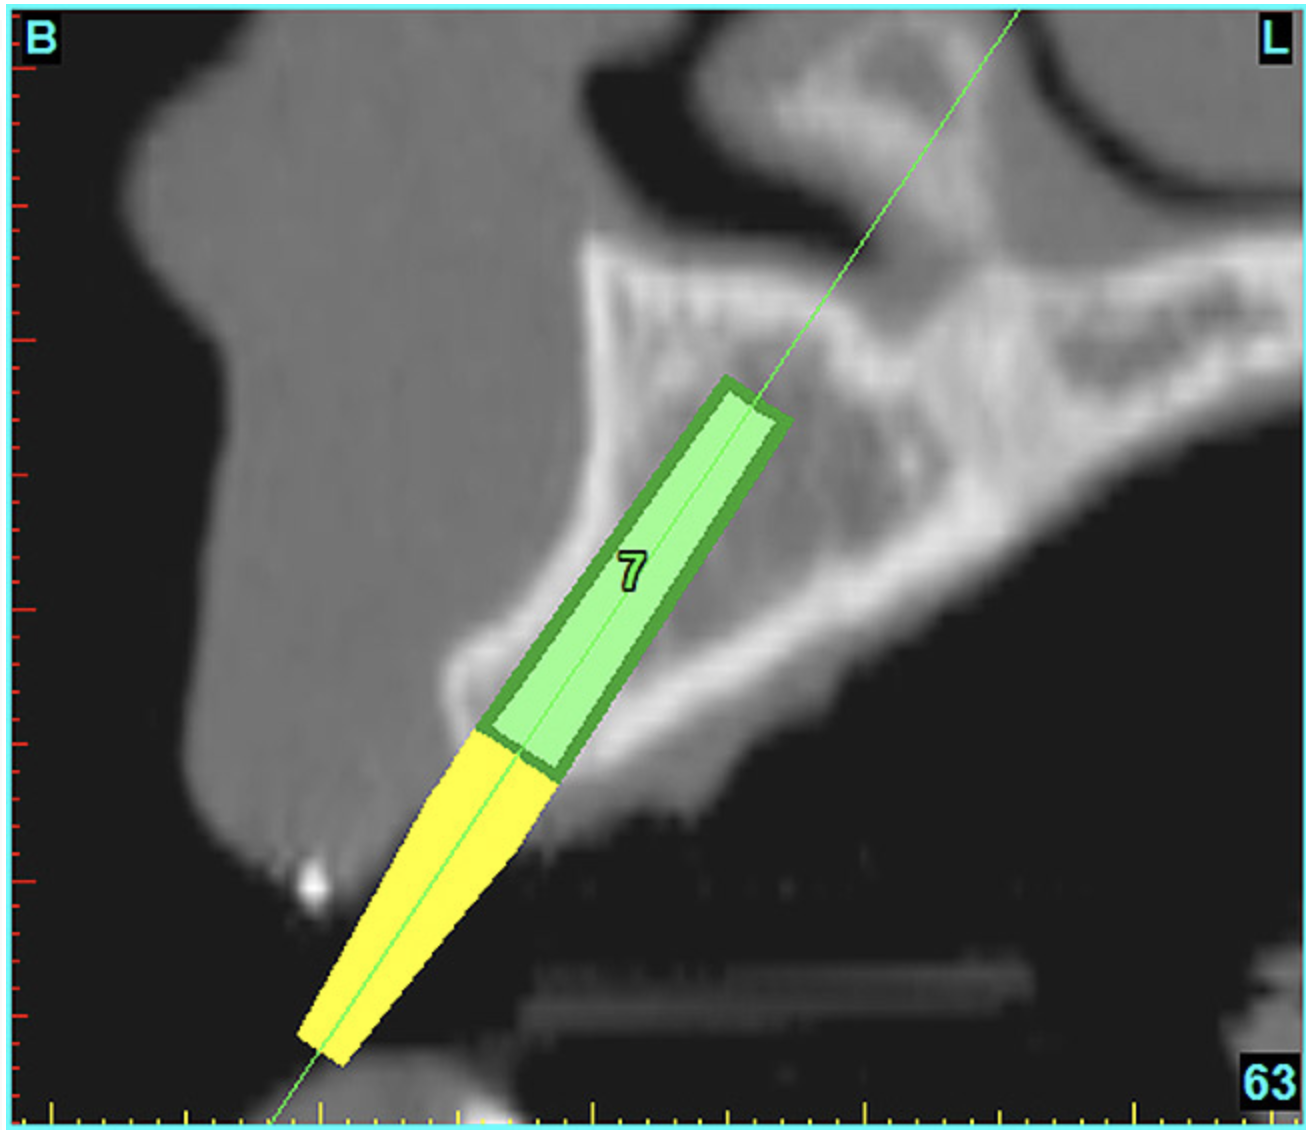

After the basic plan had been established, it was re-evaluated using interactive 3D images. The reconstructed 3D view of the maxilla clearly illustrated the extent of the bilateral facial concavities, and the root eminences of the adjacent and posterior teeth (Figure 7A). The placement of the virtual implants then was evaluated to ensure that the facial cortical plate was not perforated (Figure 7B). The implants were labeled individually as “7” and “10,” with the simulated yellow abutment projection indicating the facial-lingual inclination through the bone to the level above the incisal edge of adjacent teeth. The ability to gain a better understanding of these individual root forms can not be underestimated. The dental literature has suggested certain parameters for placing implants near teeth and implants next to other implants. However, there is little scientific 3D documentation to support these suggested rules.5-10 The use of an interactive treatment-planning software application permits closer scrutiny of previously difficult-to-visualize areas, and can now be used to redefine perceptions of spatial positioning of implants, especially when in close proximity to natural tooth roots, vital anatomy, and adjacent implants.27-29

Figure 7a  The 3D reconstruction showed (A) the facial concavities and root eminences, and allowed (B) for evaluation of virtual implant placement to ensure the facial cortical plate was not perforated.

Figure 7b  The 3D reconstruction showed (A) the facial concavities and root eminences, and allowed (B) for evaluation of virtual implant placement to ensure the facial cortical plate was not perforated.

Figure 7b